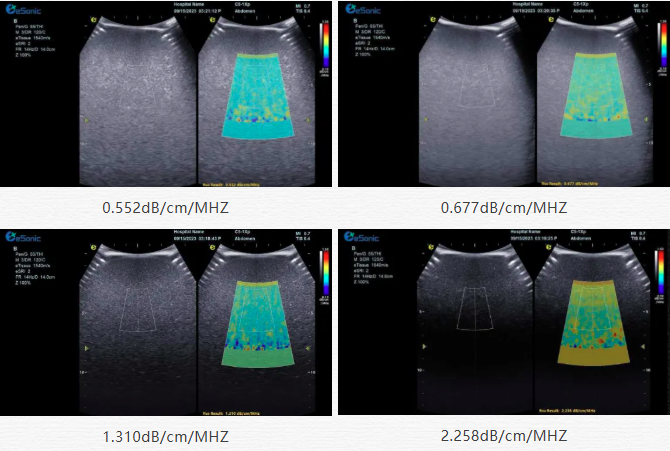

该技术基于声波在介质传播时的衰减,衰减由声吸收、反射、散射及波束扩散所致,声衰减系数(α,单位 dB/cm?MHz,与超声频率和传播距离成正比)可通过测定同频超声波在组织中的衰减程度,借回波信号分析预测声衰减系数或衰减率来评估组织特性。

声衰减定量成像(ATI)| 无创检测领域的革新之光(图2)

目前市面常用瞬时弹性成像或仿体参照法,存在适用性、准确性差及无衰减图局限。银河官网则采用准确度更高的 ALA 幅度损失衰减法,超声波深度传播时回波幅度渐降,其对数与深度有良好线性关系,声衰减量与传播衰减系数成函数关系,调节取样框大小位置可实时得样框内组织衰减系数,用于定量评估病变程度。